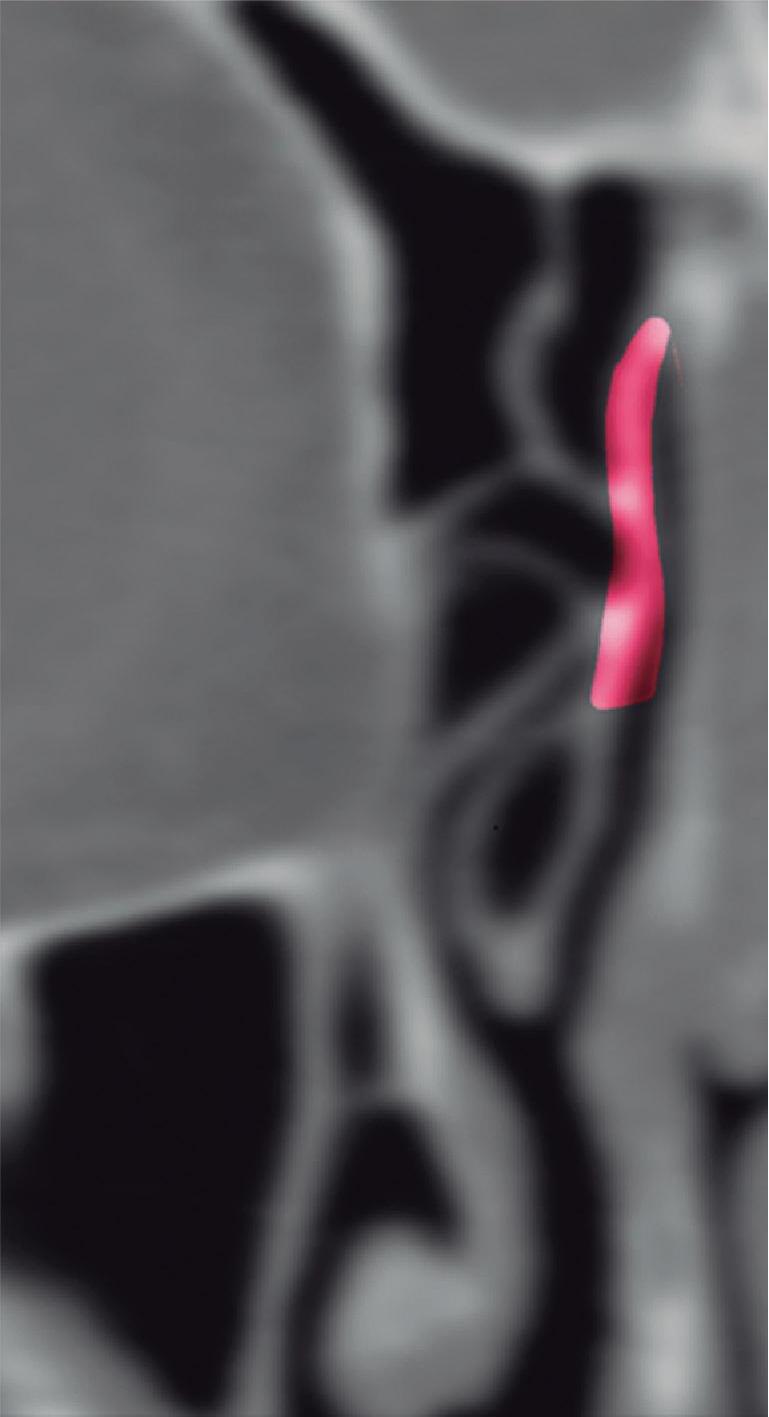

1-13. Montagem em aspecto endoscópico e peça anatômica (Bagatella) demonstrando a relação do processo uncinado e bulha etmoidal com a parede medial da órbita: (1) porção meatal da concha média; (2) processo uncinado; (3) bulha etmoidal; (4) parede medial da órbita.

1-16. Relação da bulha etmoidal com a órbita em corte axial, coronal e sagital, respectivamente.